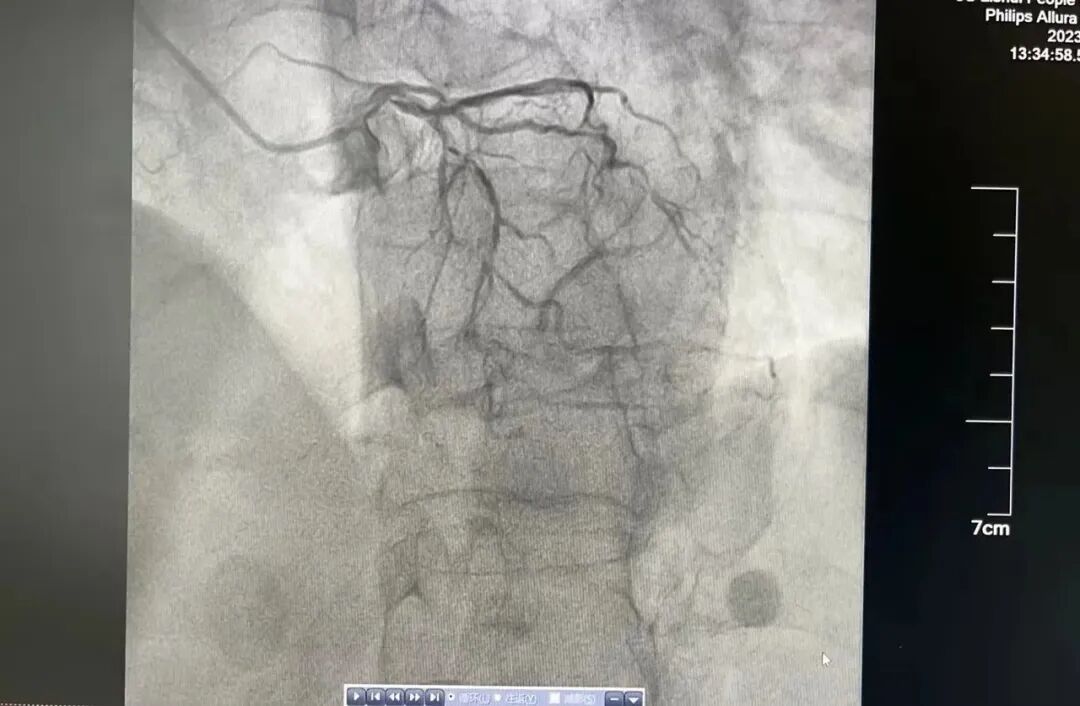

“让一让,病人要立即抢救”,一名老年女性患者正躺在推车上,向心内科导管室飞奔而去。患者持续胸痛,危重症急性心肌梗死,需要立即抢救。此时,心内科主任医师漆军华、主治医师张敦福已经在手术室等待。 漆军华了解到,患者有高血压及劳力性胸痛20多年,3天前起反复胸痛,此次因胸痛持续就诊,结合心电图判断,患者很可能冠脉病变复杂,遂立即向心内科主任陈立娟汇报病情,陈立娟主任指示立即行冠脉造影。 果不其然,冠脉造影结果显示严重三支病变,左主干疑似夹层,左前降支全程严重钙化纤细伴重度狭窄,左回旋支开口狭窄95%以上,可见左冠向右冠提供侧枝循环,右冠状动脉巨大,全程严重钙化,中段完全闭塞,且患者持续胸痛不缓解,血压偏低,基本可以判定患者病情危重,随时有生命危险。 陈立娟仔细查看造影影像后,判断立即行血运重建是拯救患者生命的唯一出路,溧水区人民医院导管室有抢救危重患者的利器——主动脉球囊反博(IABP),建议在主动脉球囊反博(IABP)支持下进行手术。 得到家属同意后,值班护士张燕萍、周红迅速启动IABP机器,配好抢救药品,陈立娟与漆军华穿上铅衣准备上台。看着严阵以待的心内科团队,家属对医院充满了信赖。 手术准备就绪,陈立娟和漆军华迅速穿刺股动脉,送入IABP球囊,两位护士熟练地连接好主动脉球囊反博仪并打开机器,此时患者胸痛有所减轻。左指引导管到位后,工作导丝通过前降支病变送至远端,但因患者冠脉钙化严重,即使最小的球囊也无法通过病变。 面对困境,陈立娟果断改变思路,患者右冠巨大,供血范围极大,如果能开通右冠,有极大的可能性保住患者生命线,幸运的是,在微导管后支撑下,工作导丝很快就通过了中段闭塞病变,随后在右冠植入支架,支架植入后,患者胸痛明显缓解,生命危险终于解除。手术很成功,患者术后转中大医院继续治疗,目前恢复良好,已经出院。